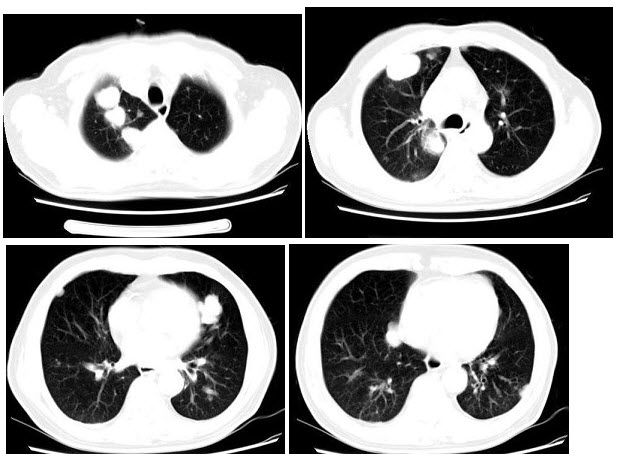

C.全大脑半球裂

男,40岁,化脓性胆管炎手术后3天出现高热,伴胸痛,咳嗽,CT如图,最可能的诊断为()

A.肺转移癌

B.金葡菌肺炎

C.肺淋巴瘤

D.肺多发性脓肿

E.肺组织胞浆菌病